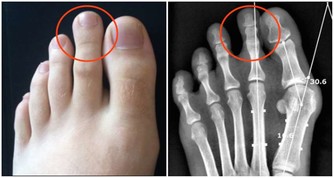

手掌青筋——積滯脾虛多便秘 如果手掌到處可見青紫色的「青筋」,表示腸胃積滯、淤血積聚,提示腸道有積滯宿便,多患有習慣性便秘、痔瘡等。常見不適表現為頭暈、頭痛、疲倦乏力、脾胃虛弱、便秘等。 調理方法:1.居家飲食可以多吃高纖維的食物,包括香蕉、豆類、橙子等。2.如果需要通過中醫調理,久治便秘無效可以選擇火麻仁丸;如果不是很嚴重的便秘則可以在平時選擇生地、玄參、首烏煮水喝,每次20~30克補血調理即可。